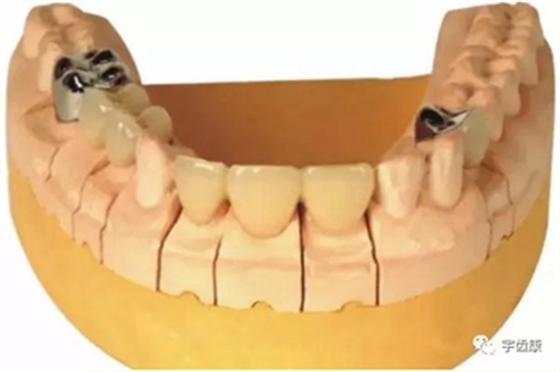

7. 共同就位道的調(diào)節(jié)

多個基牙時就位道的調(diào)節(jié)